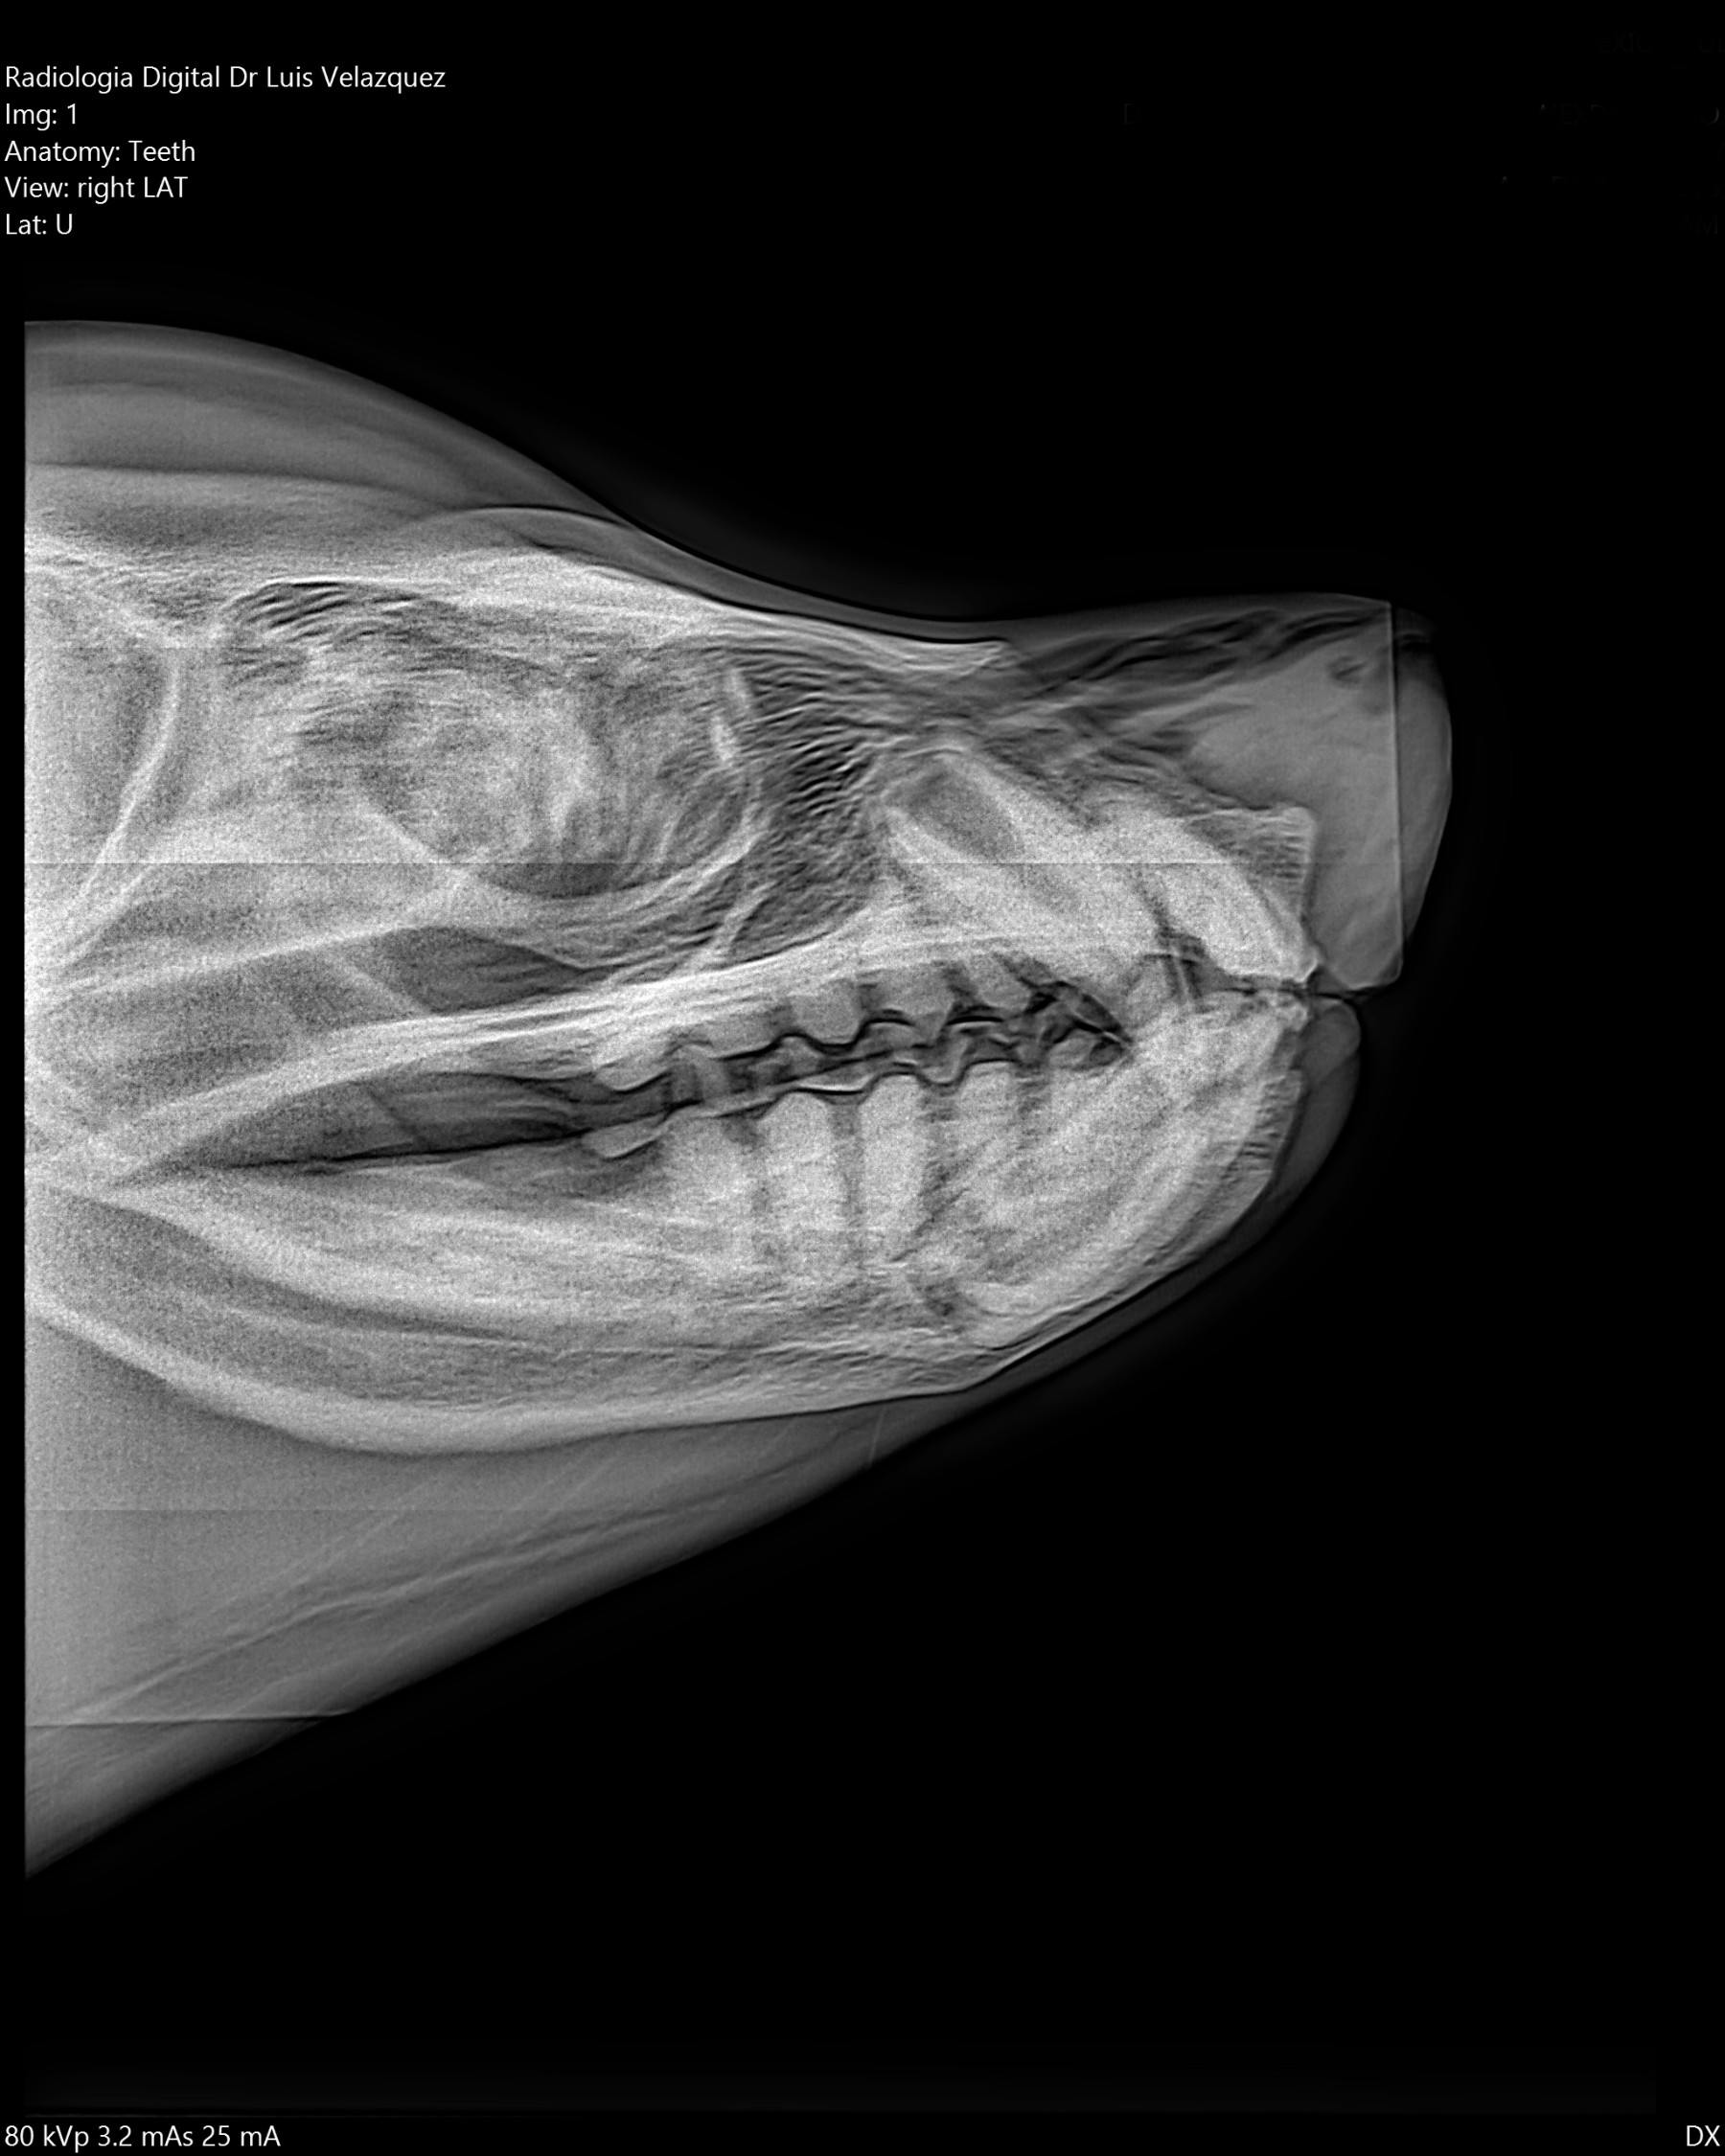

Radiología Digital como Herramienta Complementaria en el Dictamen de Bienes Muebles